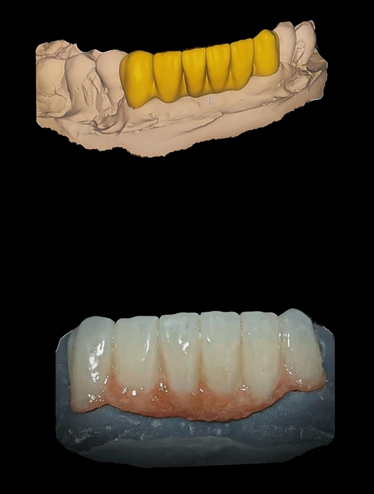

Tecnología CAD/CAM

Nuestro laboratorio cuenta con la tecnología CAD/CAM más avanzada, que nos permite diseñar y fabricar prótesis dentales personalizadas con precisión y velocidad.

– Diseño y fabricación de prótesis dentales (coronas, carillas, puentes, coronas sobre implantes , incrustaciones y impresión de modelos de trabajo en 3D.

Trabajamos en materiales como el zirconio, Disilicato de litio, PMMA y Ceromero)

Coronas y Puentes en Zirconio